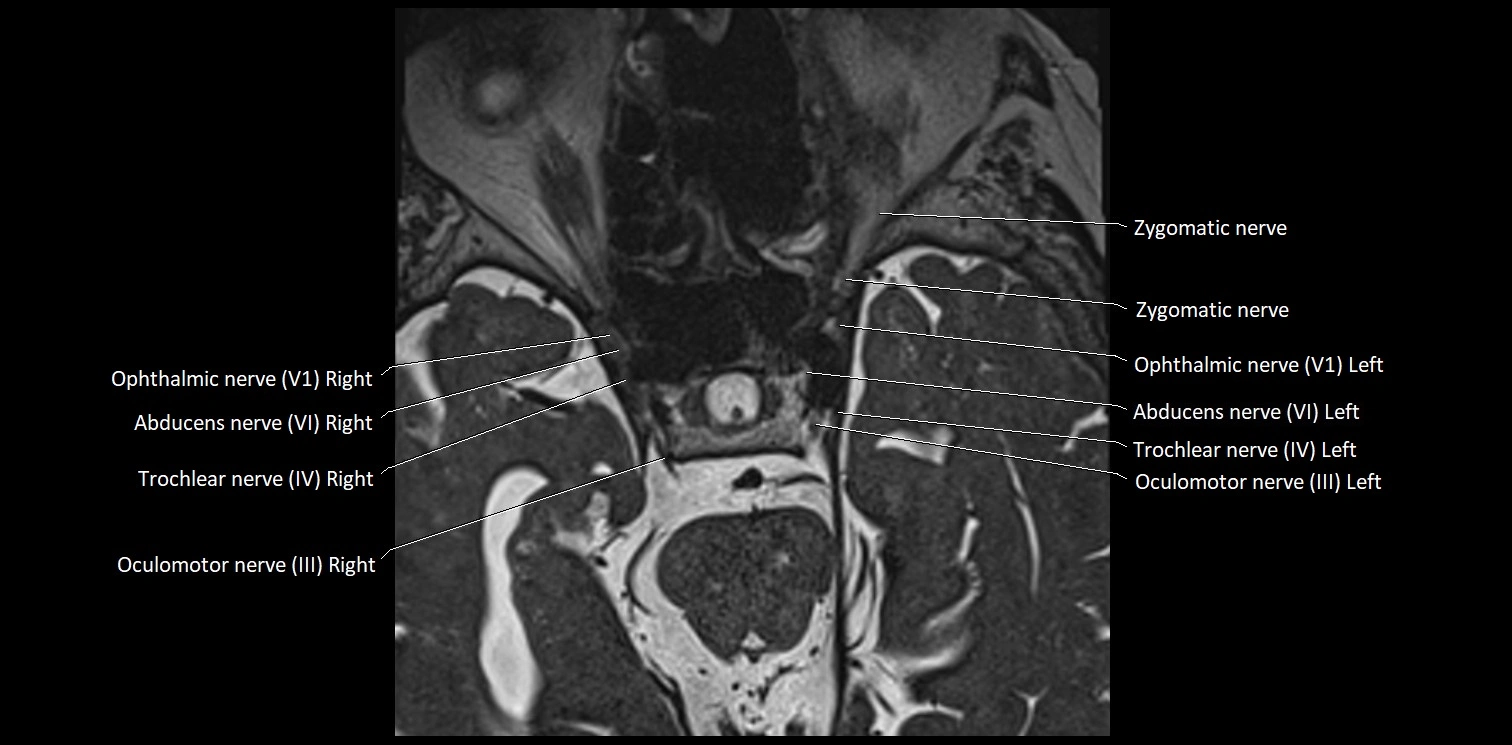

MRI Appearance

• The abducens nerve is a small, thin, linear structure

• Best visualized on high-resolution T2-weighted 3D MRI sequences (e.g., FIESTA or CISS)

• Seen as a hypointense (dark) line running from the brainstem at the pontomedullary junction, traversing the prepontine cistern, and entering Dorello’s canal under the petrosphenoidal ligament, then into the cavernous sinus, and finally the orbit

• May be challenging to visualize in standard MRI due to its small size

• Pathology may be inferred by absence, displacement, or enhancement of the nerve

MRI images

image